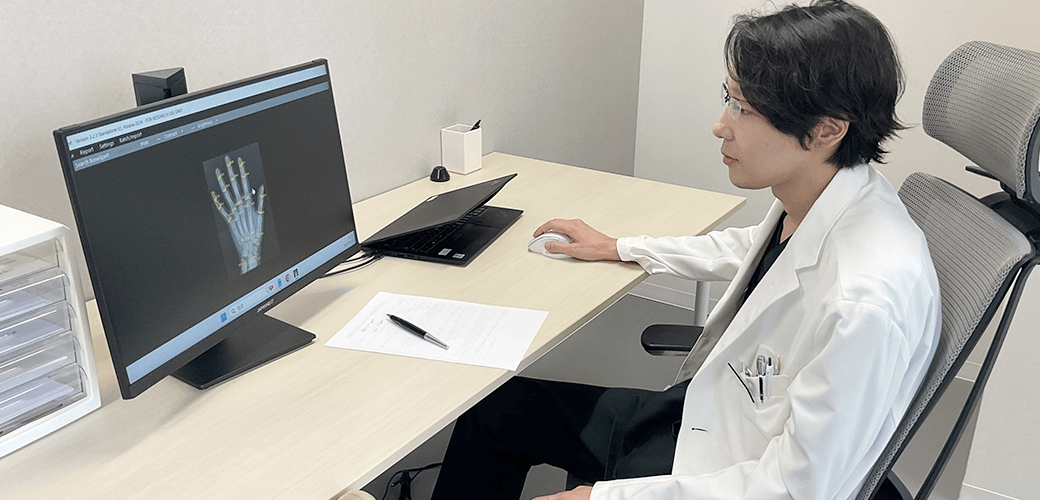

成長ホルモン療法の適否を見極めるためには、現在のお子さまの成長段階を医学的に正確に把握することが何よりも重要です。当院では、最新の画像解析技術とAIを組み合わせた評価システムを導入し、従来よりも安全かつ高精度な診断を可能にしています。

低負担X線装置による骨年齢評価

お子さまの手のX線画像で「骨端線」の状態を確認し、骨年齢を測定します。使用するのは医師監修のもと独自開発した低負担のX線撮影機器で、身体への配慮を重視した設計です。撮影は左手のみで行うため、負担を抑えた検査が可能です。 お子さまの安全を第一に考えた検査体制を整えています。

AIによる骨年齢解析システム

取得したX線画像は、AIによる高度な画像解析技術により数値化され、骨年齢と今後の成長予測を導き出します。このシステムは、医師の目視による主観的な評価に比べ、精度・再現性ともに非常に高く、診断の客観性を大きく向上させるものです。医師の診断にAIのデータを掛け合わせることで、より的確な成長評価・治療計画が可能となります。